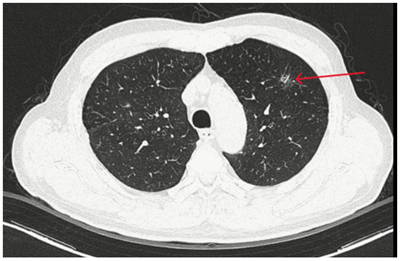

Case lâm sàng: Ứng dụng trí tuệ nhân tạo (Artificial intelligence – AI) trong chẩn đoán và điều trị sớm Ung thư phổi tại Trung tâm Y học hạt nhân và Ung bướu, Bệnh viện Bạch Mai

Theo GLOBOCAN 2022, ung thư phổi đứng đầu về số ca mới mắc (2.480.301 ca mới mắc chiểm 12.4%) và dẫn đầu số ca tử vong (1.817.172 ca tử vong chiếm 18.7%) trên toàn thế giới.  Tại Việt Nam tỷ lệ mắc ung thư phổi xếp thứ ba 13,5% lệ tử vong...